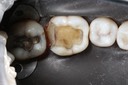

Gary Umeda #18-19 composite removal

Gary Umeda #19 buccal